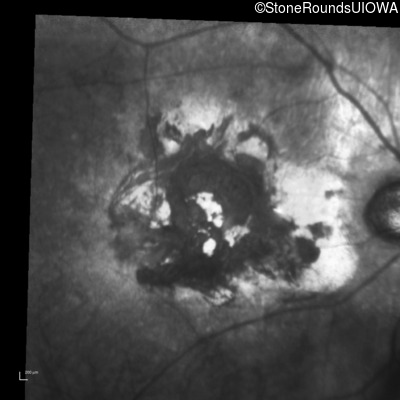

Infrared Fundus Photograph - Right - Count Fingers 2'

Exemplar